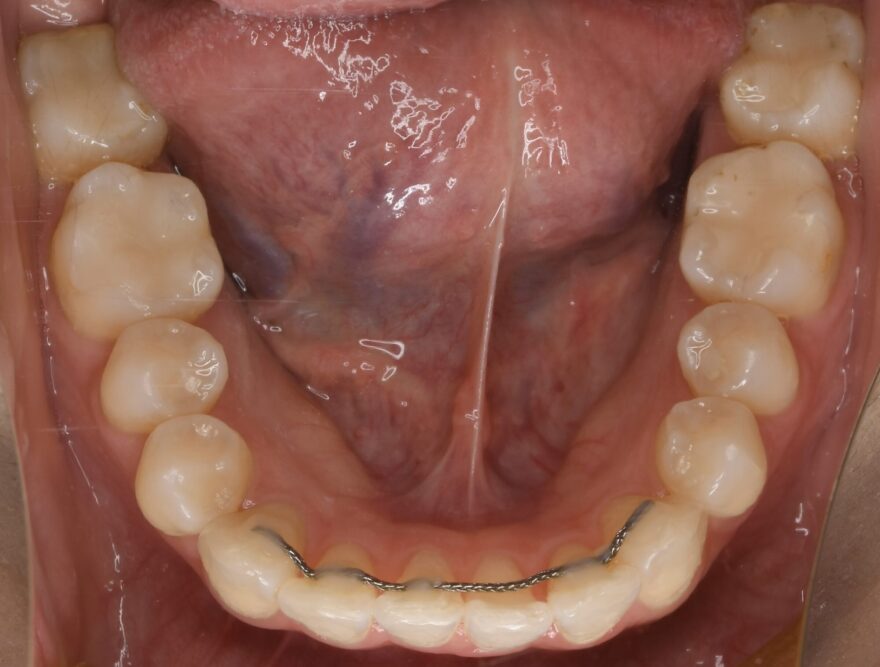

矯正治療終了時の口腔内写真

左右の奥歯4本には白い樹脂が入った状態で、矯正治療を進めてきました。

こちらも目立つ銀歯をまず樹脂で白くしてから矯正治療をスタートしました。